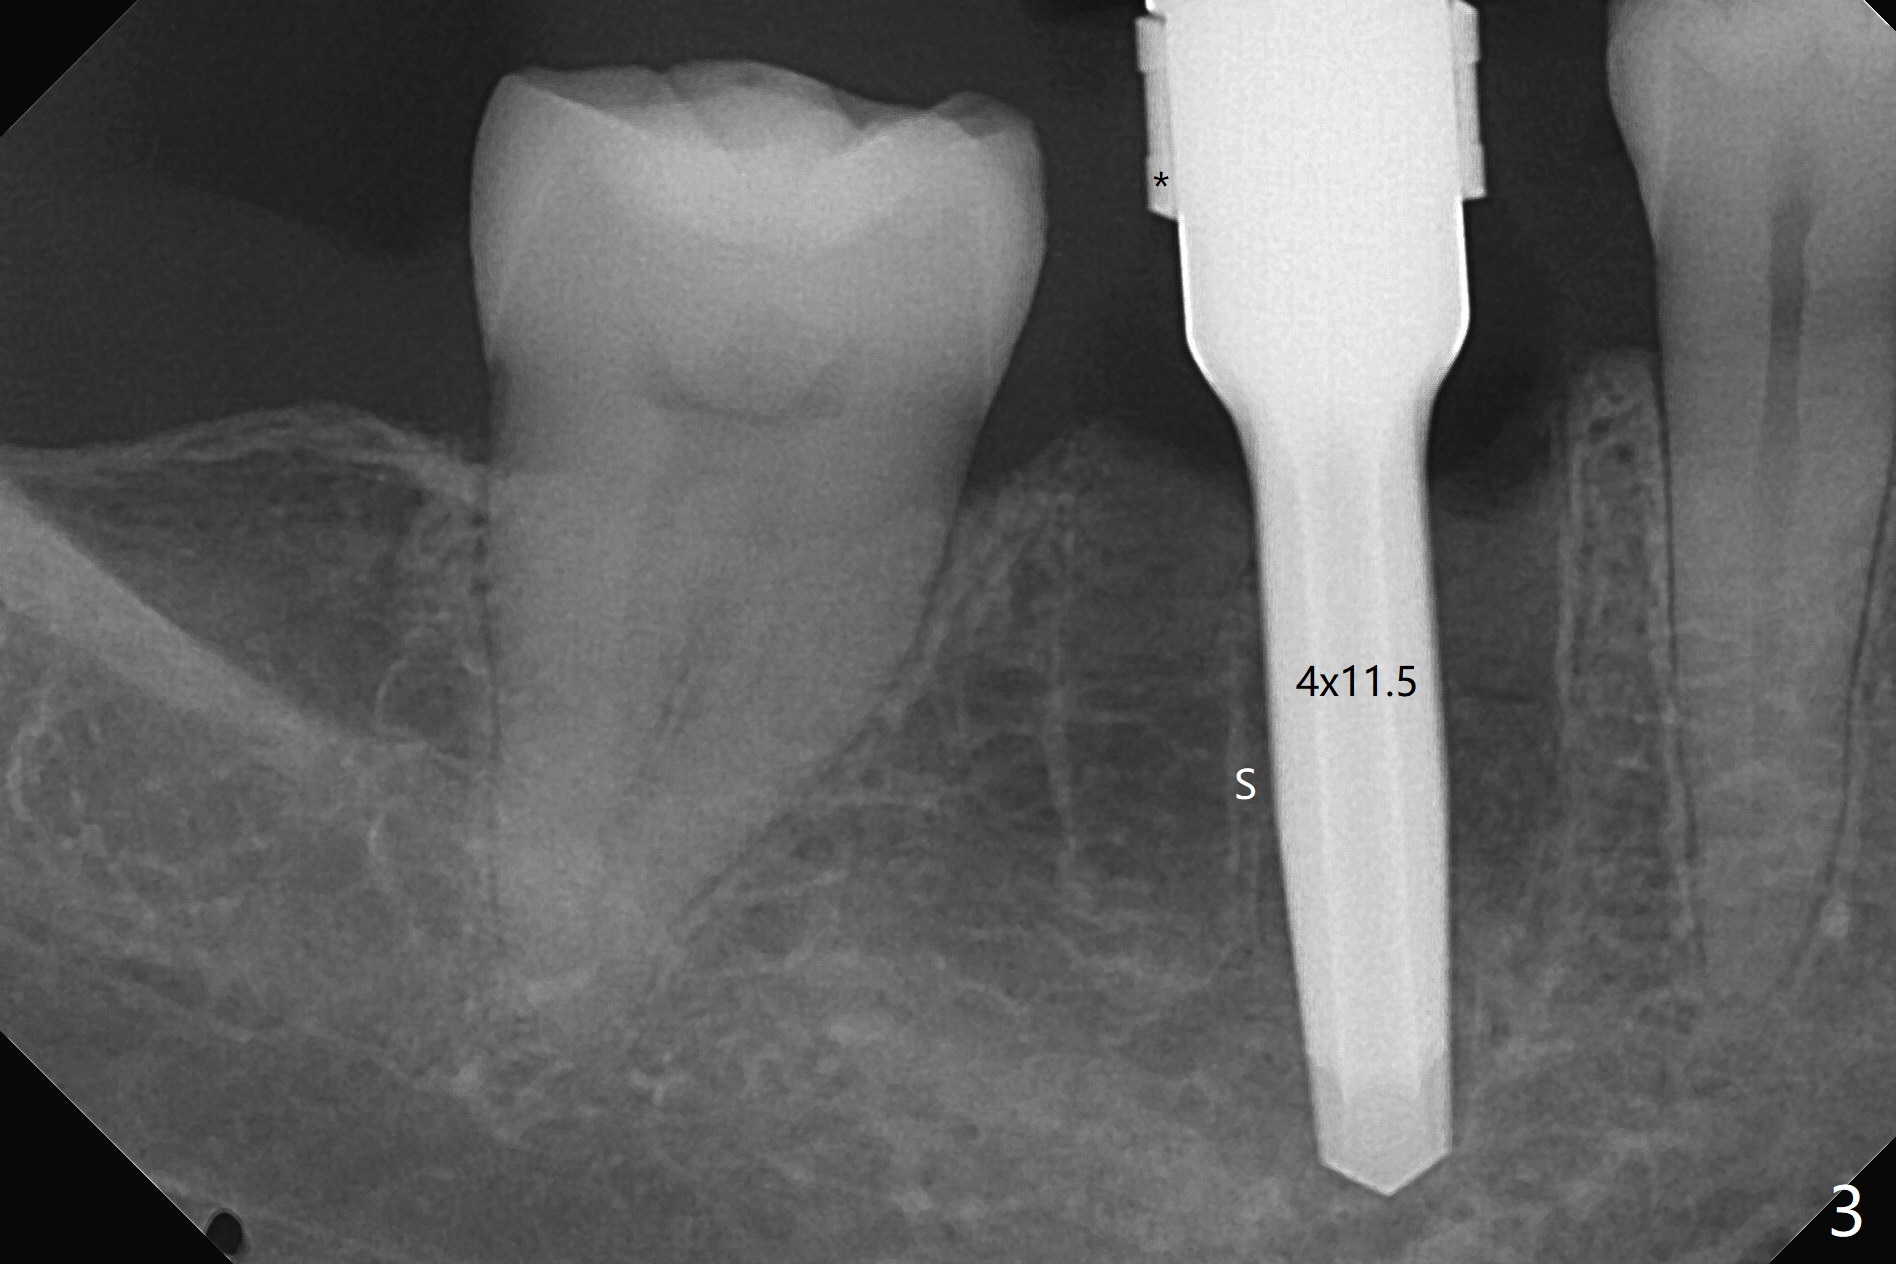

To prevent further postop buccal gingival recession at #30, socket shield is formed with removal of the residual roots (Fig.1,2 *). Osteotomy is initiated in the septum (Fig.2 S, to be flattened with bone trimmer and surgical round bur) and gradually slides slightly into the mesial socket in spite of using surgical guide (Fig.3 *: sleeve). Following 4.5x11.5 mm drill, a 4.5x8 mm Bicon implant is pressed fit; its stability is lightly enhanced with placement of sticky bone in the remaining sockets (Fig.4 *) and around the black plug (Fig.5 P). After removing the coronal portion of the plug to reduce occlusal interference, two pieces of PRF are wrapped around the remaining plug (Fig.6). The main stability of the implant is obtained when setting acrylic (A in Fig.7) is applied into the edentulous space (undercut). After acrylic setting, flowable composite (*) is added distal for further retention. One month postop, the flowable composite is detached. The provisional is sectioned; the black plug is cut. The socket heals with exposure of the mesial socket shield (Fig.8 >). The black healing plug and the mesial socket shield remains exposed 3 months postop (Fig.9). When a 4.5x6.5 mm temporary abutment is placed, the buccal gingiva is blanched and the mesial socket shield is pushed buccal (Fig.10). The implant appears to remain covered by the bone 3 months postop (Fig.11). Cortical bone starts to form crestal 7 months postop (Fig.12 arrowheads, coronavirus). The cortex seems to thicken 8 months postop (Fig.13 *).